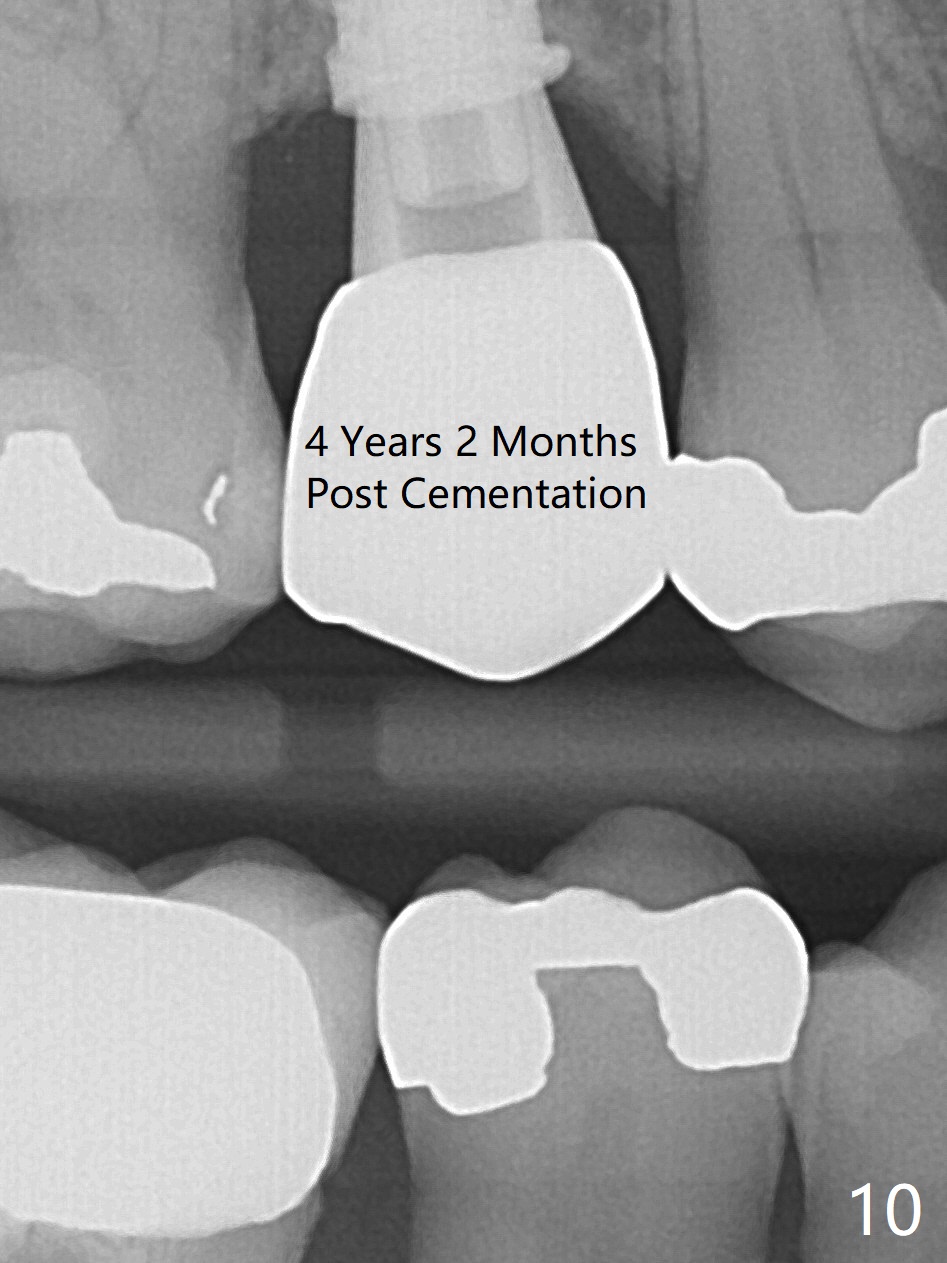

To prevent sinus lift related sinusitis, a shorter implant is going to be placed (Fig.1), approximately 2 mm beyond the apex.  Following extraction, the buccal plate (Fig.3a (coronal section): B) is not only ~ 2 mm shorter than the palatal one (P), but also thinner.  Since the bone density of the palatal plate is higher, without osteotomy an implant is less likely placed in the middle of the socket (S (Fig.1); Fig.3b) than buccal (Fig.3c).  Therefore drills are used to form osteotomy in the apical 1/3 of the palatal slope (Fig.3d (red arrow); SM: sinus membrane).  When 3.3 mm Magic Drill (MD) is in place (Fig.2), the distal surface of the sinus septum is perforated without air leakage.  Demineralized allograft (.0125-.085) is placed for sinus lift (Fig.4 *) prior to placement of 4.5x11 mm implant with ~ 30 Ncm.  The implant is slightly buccal to the ideal position indicated in Fig.3e (curved blue line: sinus lift).  A 4.5x4(2) mm pair abutment is placed for an immediate provisional to hold mineralized allograft in the remaining socket gaps (Fig.4 arrowheads, .5-1.5 mm).  A 9 mm implant may avoid sinus floor perforation on the distal slope of the 2nd premolar.  The osteotomy should have been established initially as mesial as possible.  In fact the patient has nasal hemorrhage while sneezing for the first 2 days postop.  Although he complains of pain buccal to the implant, the gingiva appears to heal 7 days postop (Fig.5).  The distobuccal papilla appears to be displaced somewhat.  Raising mucoperiosteal flap is most likely associated with postop pain and esthetic compromise.  The implant appears to have osteointegrated 5 months postop (Fig.6).  A 4.5 mmx15° 3 mm cuff angled abutment is placed for final restoration.  The distolingual portion of the implant is supported by the regenerated bone 3 years post cementation (Fig.7,8).  There is no bone loss 4 years 2 months post cementation (Fig.9,10).